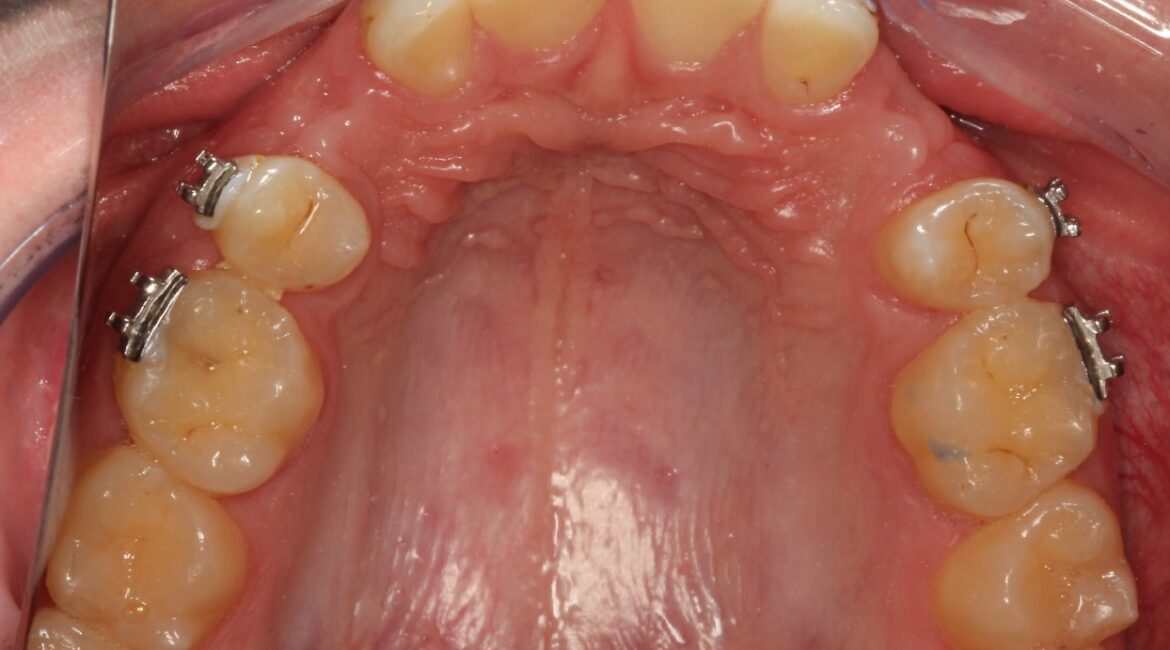

Embora seja uma má formação que se origina desde o nascimento, a agenesia dentária é mais comum nos dentes permanentes, em especial nos pré molares e incisivos. Ela pode afetar somente um ou diversos dentes de forma simultânea.

Quando a agenesia atinge até cinco dentes, é chamada de hipodontia; em seis ou mais dentes, é denominada de oligodontia. Na ausência total dos dentes permanentes, o quadro se chama anodontia.

Durante a visita, o dentista pode solicitar exames de imagem, como a radiografia panorâmica, para comprovar se o dente está somente incluso (ou dentro do osso, muito comum com os dentes do siso) – e que pode não caracterizar uma agenesia – ou a sua real ausência.

Existem algumas opções de tratamento para a agenesia dentária, a depender da quantidade de dentes afetados, sua disposição na arcada e o espaço deixado por eles.

Outra opção, caso o espaço tenha uma proporção diferente, são os aparelhos ortodônticos para ajustar o alinhamento e, posteriormente, realizar um tratamento com implantes dentários, caso o tratamento ortodôntico não seja suficiente de maneira individual.